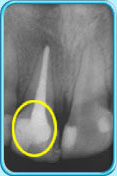

图中所见是一张X光片,显示一颗牙髓已坏死的恒门牙。治疗前

图中所见是一张X光片,显示一颗接受了清除全部牙髓的治疗之后的恒门牙。治疗后